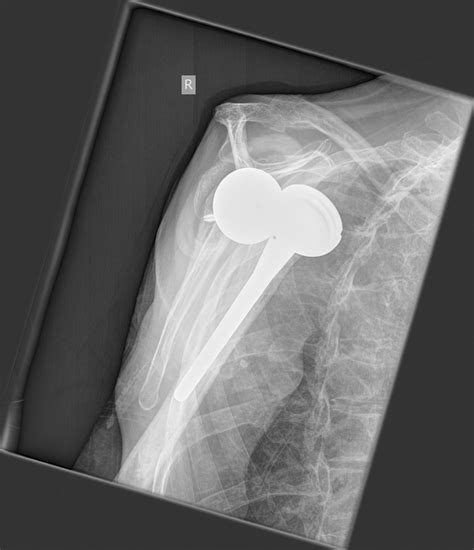

• Imaging Tests: X-rays, MRIs, or CT scans to evaluate the extent of the damage and plan the surgery.